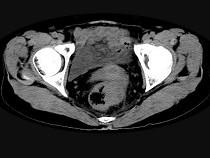

问题 男,56岁,排便形状改变,便不尽感,CT检查如图所示,下列说法正确的是()

选项 A.肠壁上有蒂状新生物 B.其表面光滑,边界清楚 C.肠腔未见狭窄 D.此为直肠息肉 E.此为直肠癌

答案 E